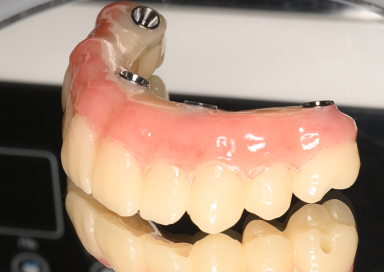

All-on-4(オールオンフォー)は、上顎・下顎に4本ずつのインプラントを埋入し、

その上に全ての人工歯を固定する画期的な治療法です。

従来のように10本以上のインプラントを必要とせず、

骨のある部分を活かして傾斜埋入することで、骨移植なしでも対応できるケースが多いのが特徴です。

Nobel Biocare純正パーツのみを使用した公式プロトコールによる“本物のAll-on-4”

Point02

Nobel Biocare純正パーツのみを

使用した公式プロトコールによる

“本物のAll-on-4”

All-on-4の開発者のDr Pole Maroの咬合哲学と設計思想を忠実に守り、非純正パーツによる破損・不適合リスクを避け、長期的に安心して使える正規クオリティの治療を提供します。

デジタル精密設計×審美再建“美しく噛めるAll-on-4”

Point03

デジタル精密設計×審美再建

“美しく噛めるAll-on-4”

3DフェイススキャンやCT、口腔内スキャナーによる完全デジタルのフル設計と診断で歯と口元だけでなくお顔のバランスにも配慮した設計を提供しています。また術後のメンテナンスと清掃性を大切にして炎症や口臭トラブルを軽減します。